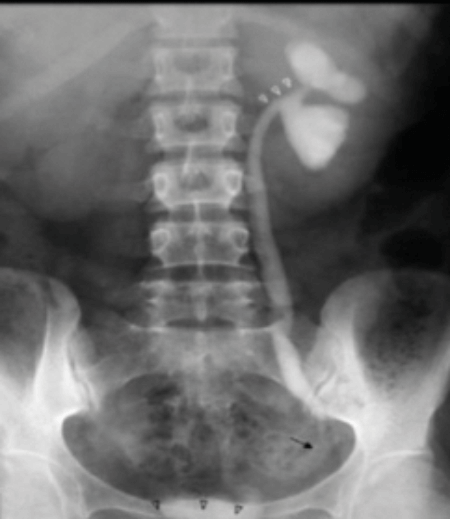

Below is a selection of radiological images of the urinary tract.

Figure 2a.

Figure 2b.

- Figure 2 shows other radiological features of one of these possible causes. What is the likely diagnosis? How often does this condition affect the urinary tract?

-

TB, 15% genitourinary tract involvement. A: left autonephrectomy, B: non-functioning right kidney with left sided infundibular scarring and caliectasis, left distal ureteric stricture, small capacity bladder.

Kidney (haematogenous spread): infundibular stenosis and calyceal dilatation, papillary necrosis, ‘putty’ kidney, autonephrectomy. Ureter: lower ureteric strictures, gold hole ureteric orifice. Bladder: ‘thimble’ bladder, calcification, reduces capacity. Rarer: prostatitis, urethritis, epidydmitis (string of beads), orchitis.

Renal calcification, infundibular stenosis, autonephrectomy, ureteric calcification / strictures, calcified bladder, small volume bladder.